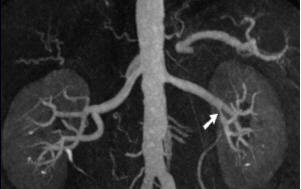

![]() |

| Coronal oblique 3D volume rendered (above) and thin MIP (below) from CEMRA, in a 60-year-old woman with uncontrolled hypertension, show beaded irregularity involving the distal right renal artery (arrows) consistent with fibromuscular dysplasia (FMD). Images courtesy of Dr. Kambiz Nael. |